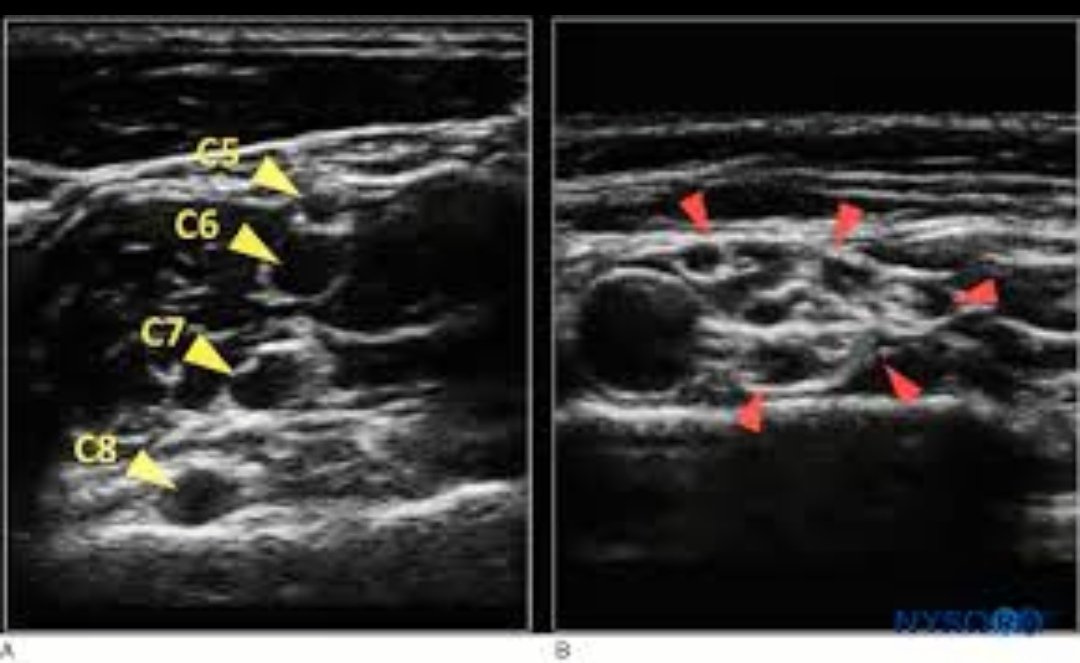

٣.الاستعانة بالاشعة فوق الصوتية "التراساوند" لرؤية العصب والانسجة المحيطة به

استخدام الاشعة فوق الصوتية لإجراء #التخدير الطرفي اكثر دقة وأمان وتزيد عندما يستخدم معه جهاز التحفيز العصبي الحركي لتحديد العصب المراد تخديره

الفيديوا يوضح كيف يقوم استشاري التخدير بتحريك الابرة الخاصة بالتخدير الطرفي حول الاعصاب وحقن الدواء #المخدر بالاستعانة بالاشعة فوق الصوتية